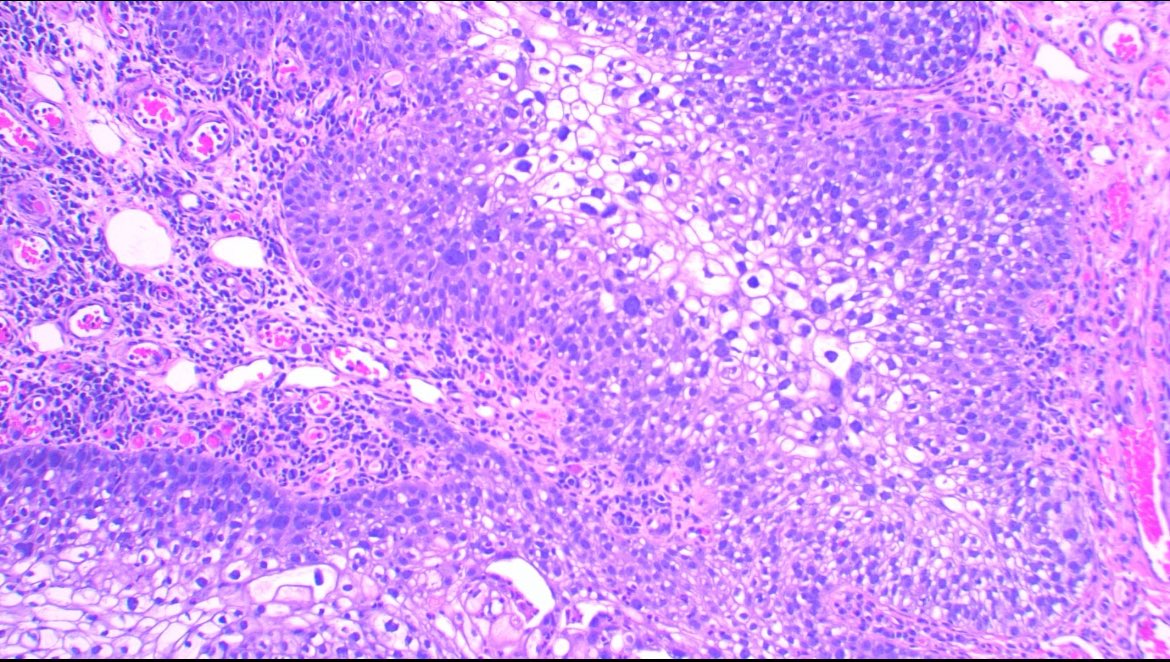

Make the Dx: ASDP October Case Study 85-year-old man with purpuric macules and papules at the abdomen, hips, and bilateral lower legs...… Learn more at asdpcasestudy.secure-platform.com/site/organizat… #asdpcasestudy; #dermatopathology; #dermpath